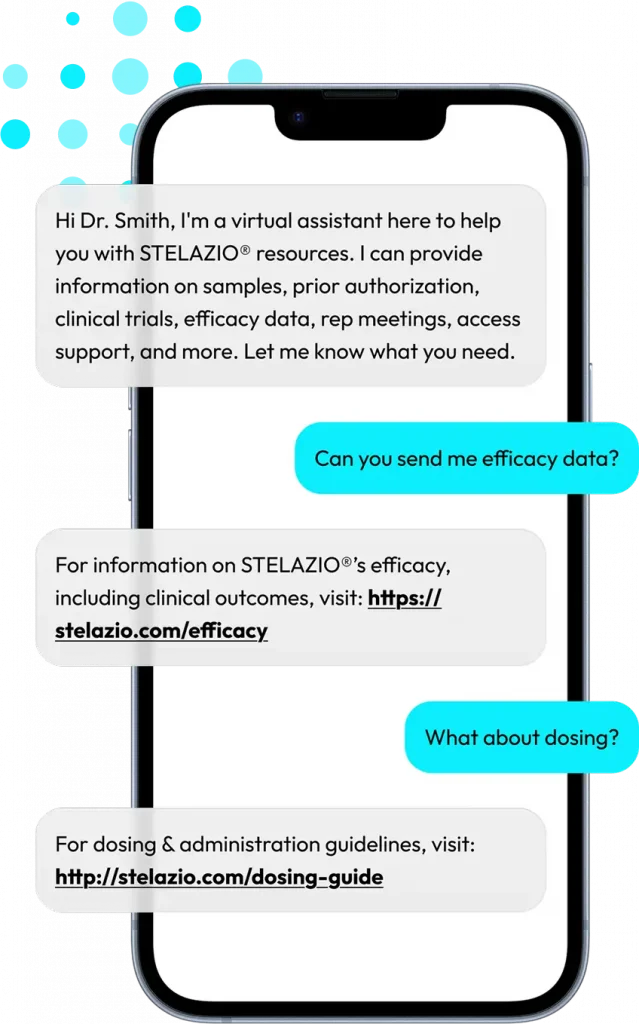

At Impiricus, we are committed to powering the next generation of ethical healthcare partnerships through dynamic, AI-powered technology. Physician and pharma evangelized, our mission is to provide life science companies with the tools they need to deliver impactful, evidence-based resources to HCPs and enhance patient care.